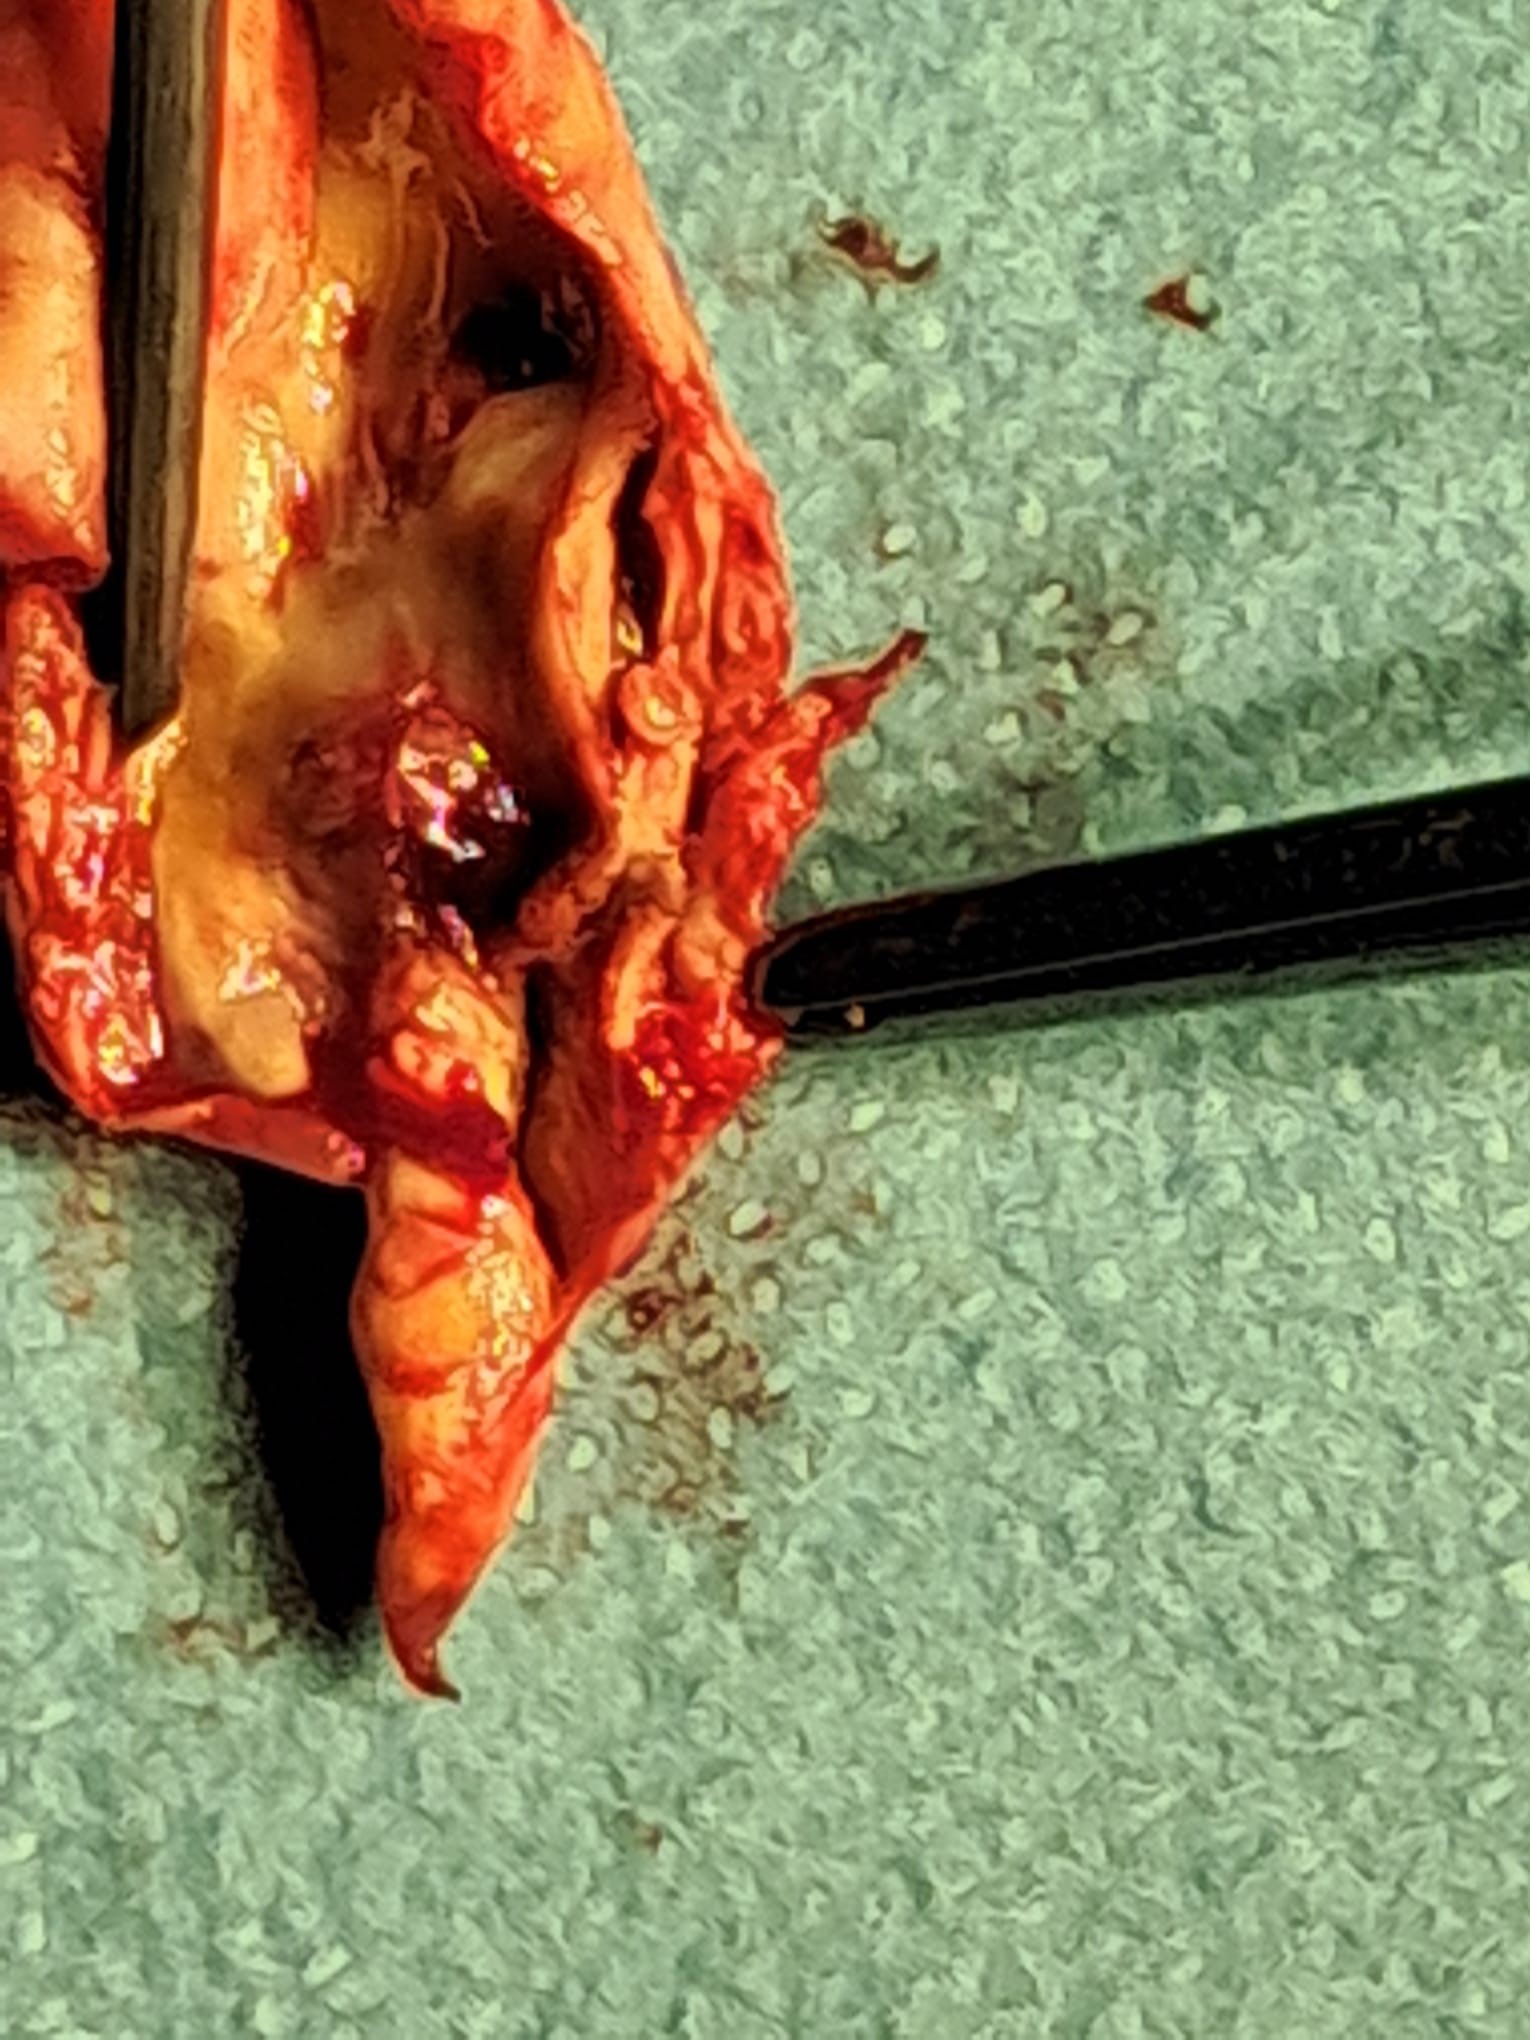

Lorsque la sténose est symptomatique ou lorsqu’une sténose asymptomatique est jugée à haut risque dans un cadre spécialisé, une revascularisation peut être discutée. Les deux grandes techniques sont l’endartériectomie carotidienne, qui consiste à enlever chirurgicalement la plaque, et l’angioplastie avec pose de stent carotidien, qui vise à traiter le rétrécissement par voie endovasculaire.